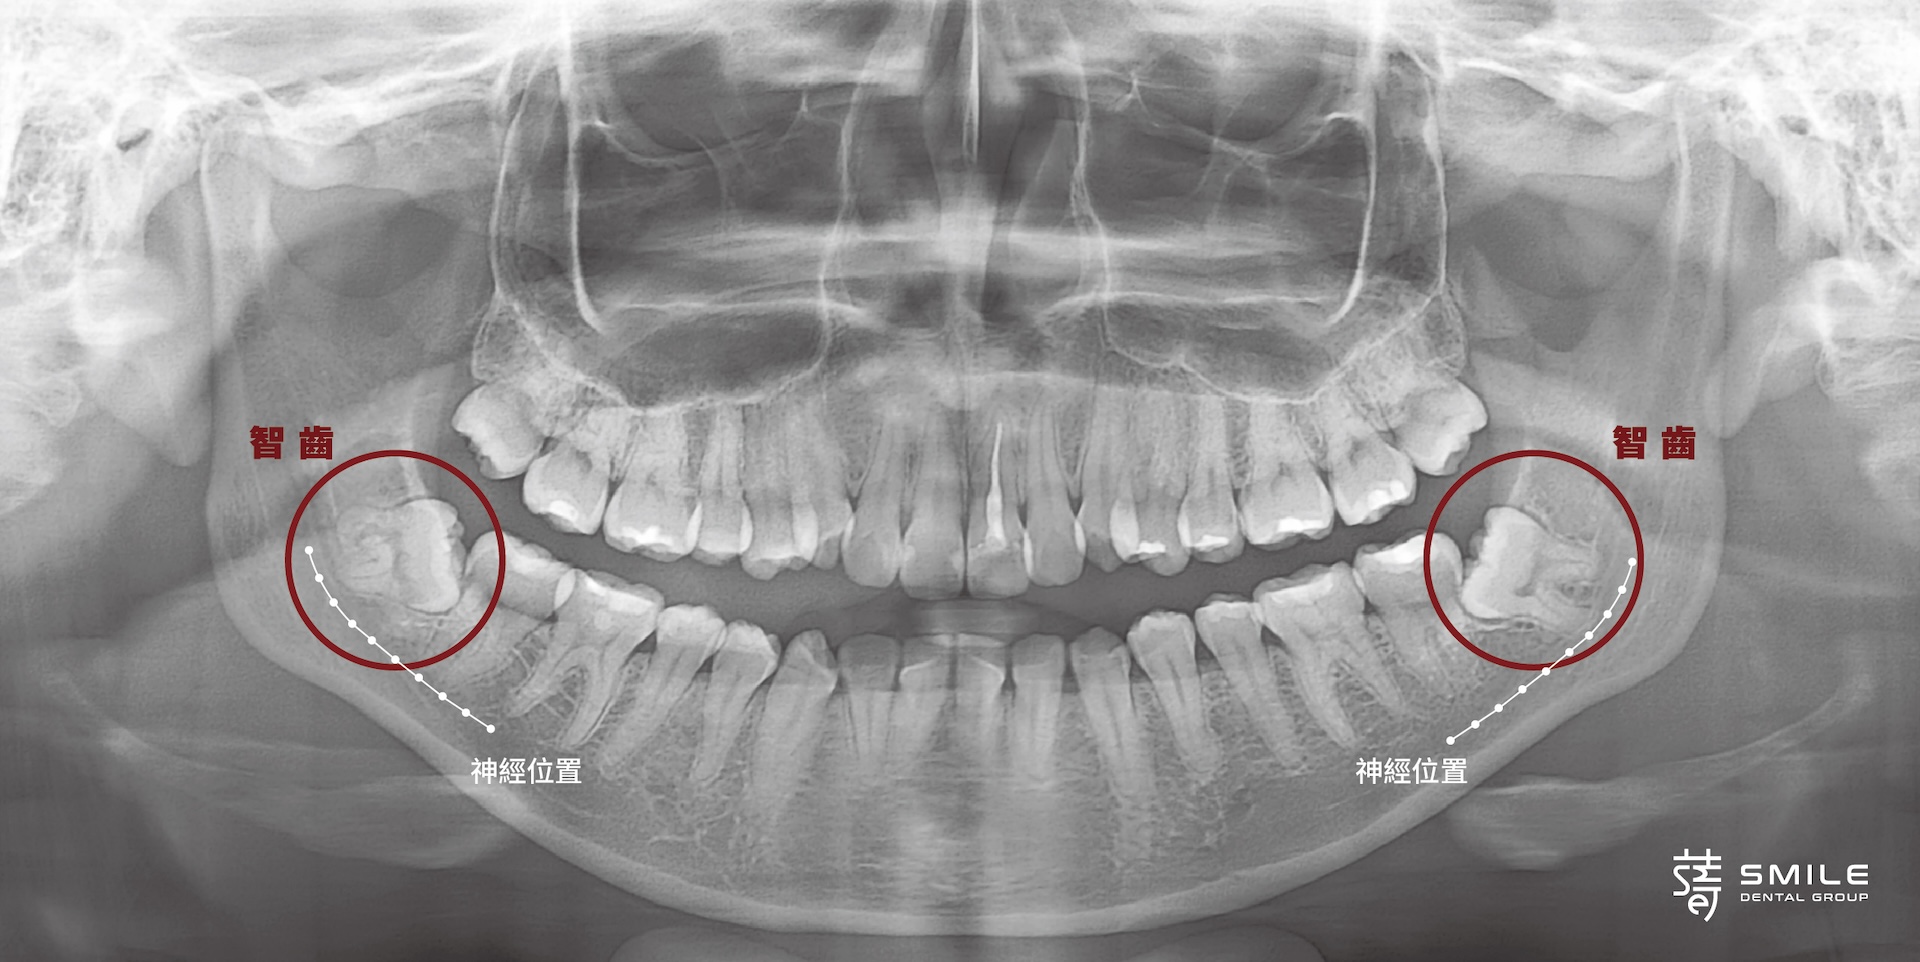

拔智齒來創造矯正空間,是常見的選擇。但在仔細分析小庭的X光後,柯醫師發現她的下排智齒長得比較靠近齒槽神經,雖然拔掉後出現長期麻木的機率不高,但風險依然存在。

Removing wisdom teeth is a common strategy to create space in orthodontics. But in Ting’s case, her X-rays revealed a different story: her lower wisdom teeth sat dangerously close to the mandibular nerve. While the risk of long-term numbness was low, it was still a risk.

聽到這樣的說明,小庭有些猶豫。柯醫師理解她的擔心,耐心陪著她,一步步討論每個可能的選擇。最後,團隊選擇保留智齒,改用其他方式慢慢創造排列空間。對蒔美來說,讓病人安全、放心是最重要的。

Understandably, Ting hesitated. Dr. Ko took the time to explain every option and walked her through each scenario. In the end, the team decided to leave the wisdom teeth intact and take a more conservative path—one that prioritized safety and peace of mind.